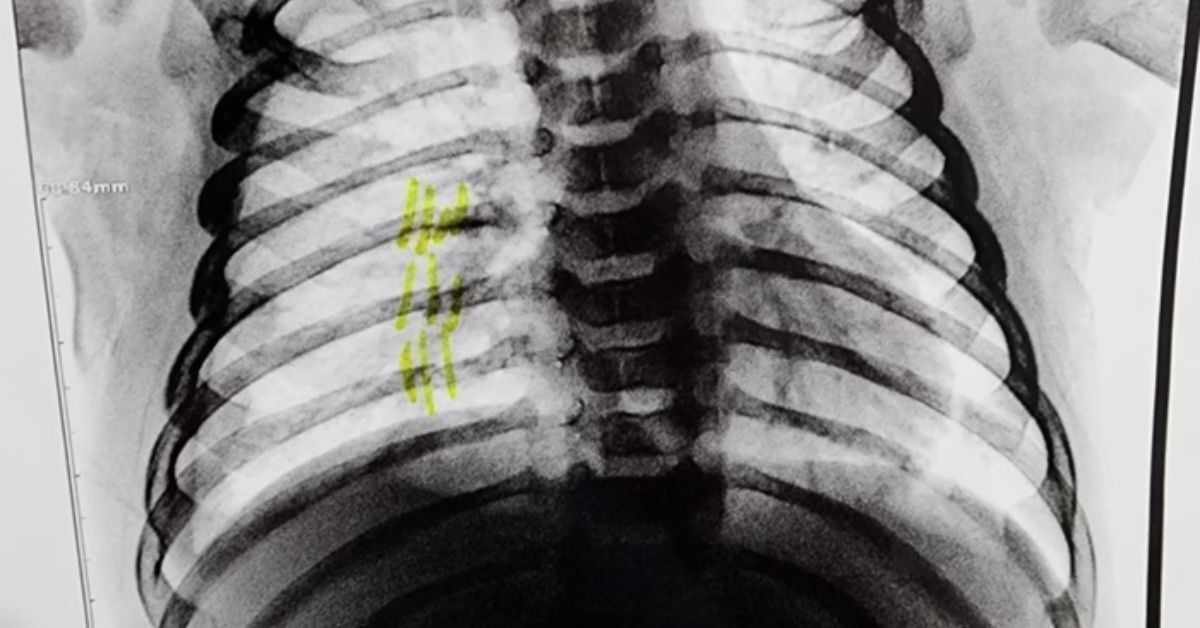

A polícia militar prendeu um homem de 24 anos, suspeito de espancar o enteado. A criança, de apenas 2 meses de vida, deu entrada no hospital e os médicos identificaram fraturas nas costelas do bebê. O caso aconteceu em Cabreúva, no interior de São Paulo. A polícia foi acionada pelo Conselho Tutelar, depois que a criança deu entrada na Unidade de Pronto Atendimento (UPA) do Jacaré.

Médicos estranharam a quantidade de ferimentos na criança e o Conselho Tutelar foi acionado. A situação gerou grande comoção na comunidade local, que se mobilizou em apoio à família da vítima.